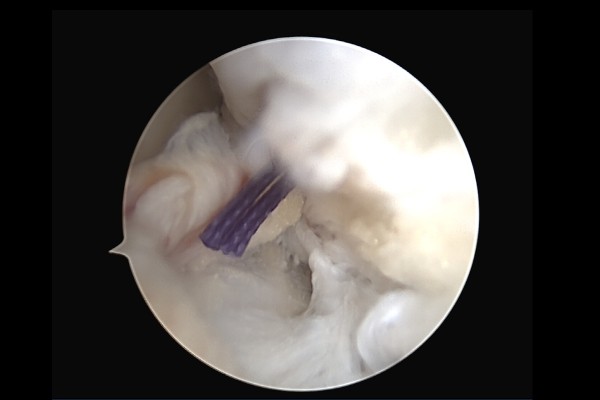

이후 인대가 붙을 부착부위에 구멍을 뚫어서 칼슘나사를 삽입해주면,

인대가 딸려오면서 부착부위에 붙게 됩니다.